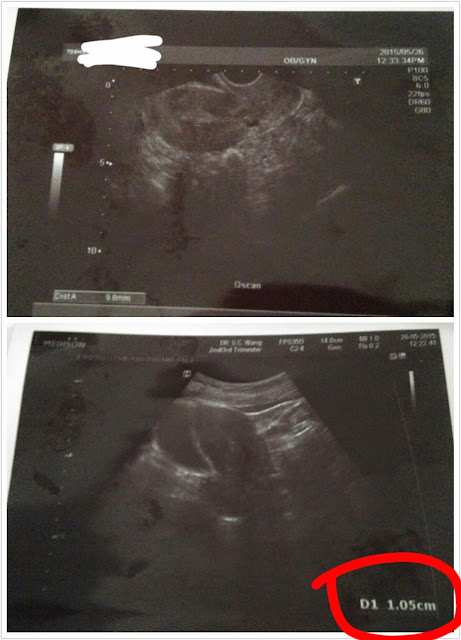

5月26日,星期二,月經週期的第四十天。

我依沈醫師的指示前往找婦科照超聲波,

目的是看看有沒有優勢卵泡,如果有便明天回去找她再針灸。

一早,我便冒著黑色暴雨前往太子找之前看過幾次的婦科女醫生黃醫生。

我告訴她今天已D40了,她馬上皺起眉頭,問我會否有可能懷孕了,

我當然認為沒有可能。

我告訴她我主要來意是想看內膜厚度及卵泡大細,

讓中醫師參考。

她先看內膜,結果十分滿意,厚度有1.05,還說這個厚度可能放胎了。

看完內膜後,被她罵了我一會兒,

問我為什麼去看中醫,說中醫拖長了我的周期,周期短一點可以多試幾次。

她說我身體沒有什麼大毛病,雖然造卵有點問題,但多試幾個月會有的,

罵我攪那麼多東西。

但卵泡呢?她說找不到,

上一次也看到一粒1.1的,但現在沒有半粒看得上的,

全部也是很細或萎縮了。

她的推論是可能已排卵了。

聽見她這樣說我感到十分意外,排卵紙未見粗深,

體溫沒有上升,拉絲也沒有看到就說我排了。